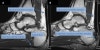

MRI : 아킬레스건염(Achilles tendinitis, Achilles tendonitis)